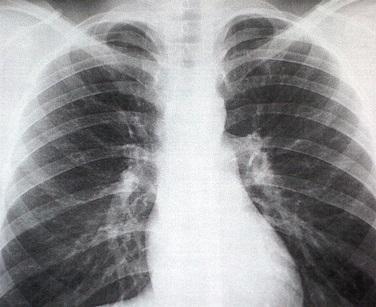

Imagem: steadyhealth.com

As fraturas de esterno, bem como as de costelas, detecta-se com um simples exame de raios X. Uma vez diagnosticada, você deverá seguir o tratamento médico recomendado e ter em conta algumas sugestões para se recuperar rápido desta lesão.